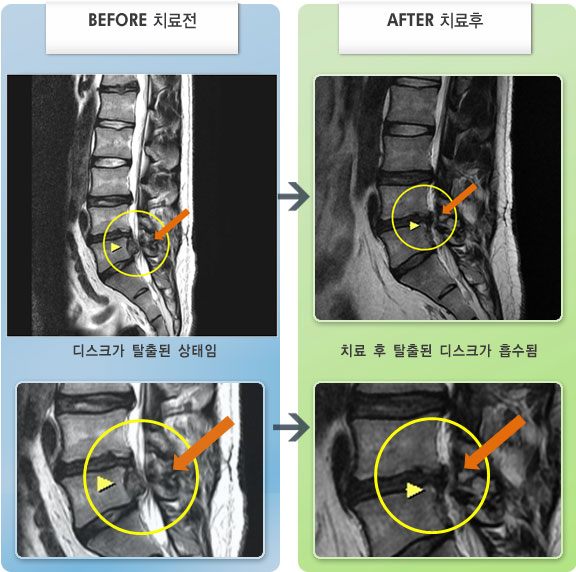

MRI 치료사례

허리디스크로 인한 좌측 하지 통증